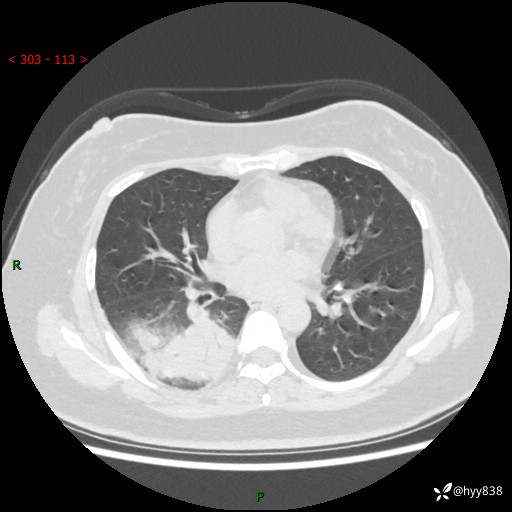

大叶性肺炎的表现形式,晒晒鉴别诊断吧…结果公布~

简要病史:患者8天前无明显诱因出现咳嗽、咳痰,为绿色脓痰,无明显加重与缓解因素,无高热、寒战,无呼吸困难,无大量脓痰,无哮鸣音,于当地医院行胸片示右下肺团块影,性质待定,予口服药物治疗症状未见明显改善,具体药名不详,为求进一步诊治来我院就诊,门诊以“肺占位性病变”收入我科进一步诊治。 患者自发病以来,精神、饮食尚可,睡眠欠佳,大小便正常,体力、体重未见明显异常。

辅助检查:CT

胸部CT平扫

增强动脉期+静脉期